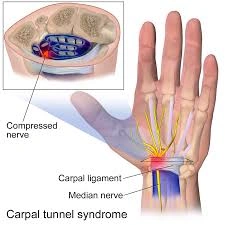

Carpal Tunnel Syndrome

What is Carpal Tunnel Syndrome?

Carpal Tunnel Syndrome occurs when the median nerve in the wrist becomes compressed, leading to pain, numbness, and tingling in the hand and fingers.

Treatment

Image-guided injections or minimally invasive procedures can reduce inflammation and relieve pressure on the nerve, improving hand function.

Common Symptoms

Numbness in fingers

Wrist pain

Weak grip strength

Tingling sensation in the hand